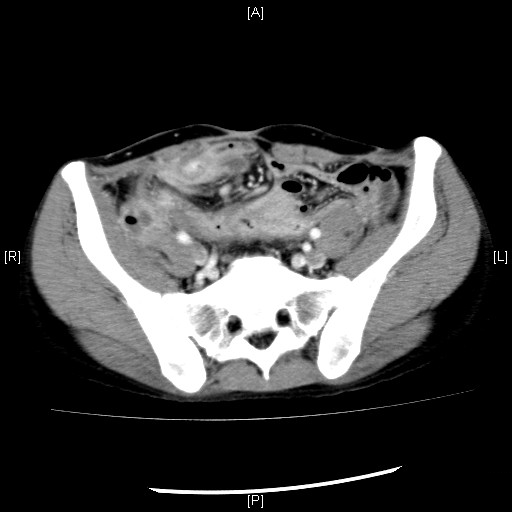

右腸腰筋膿瘍

右腸腰筋に膿瘍形成を認める。膿瘍内のガスは腸管との瘻孔またはガス産生菌の関与を疑う。